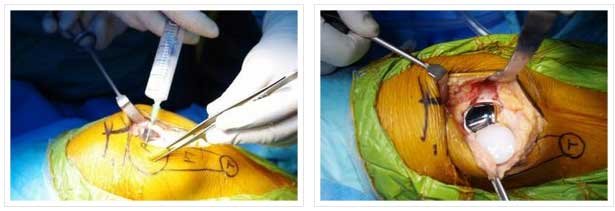

PATELLOFEMORAL

- PATELLA REPLACED WITH POLYTHYLENE INSERT

- TROCHLEA WITH UNCONSTRAINED METAL

- INLAY AND ONLAY TECHNIQUE: INLAY MY PREFERRED- LAZY

- PATELLAR TRACKING TO BE CLOSELY EXAMINED BEFORE SURGERY, MOST REQUIRE LATERAL RELEASE.

PATELLOFEMORAL ARTHRITIS IN- 40 YEAR OLD FEMALE

PATELLOFEMORAL REPLACEMENT-POSTOP